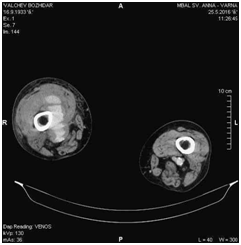

There were no significant blood test abnormalities, except elevated C-reactive protein. Electrolytes and renal function tests were normal. Performed color Doppler ultrasound of the lower leg vessels revealed an image with a greatest diameter of 38.32mm within the topography of the SFA, poorly-defined limits and mural thrombus. These characteristics suggested a ruptured aneurysm of the SFA (Figure 3). Computed tomography angiography (CTA) revealed ruptured aneurysm of right SFA with a diameter of 34mm (Figure 4 and 5).

Figure 4 CTA image showing an aneurysm of the right SFA.

Figure 5 CTA image showing an ruptured aneurysm of the right SFA.